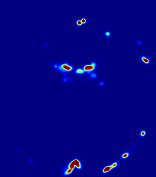

Figure 4: PIANO feature maps for another patient in the ISLES 2017 training set, where the lesion is located in the right hemisphere. Top row: segmented stroke lesion region (white) on different slices. The corresponding slices for the PIANO feature maps are shown in the following rows.

For a better insight into an estimated velocity field 𝐕𝐕{\bf{V}} and diffusion field 𝐃𝐃{\bf{D}}, we compute the following maps: (1) 𝐕rgbsubscript𝐕𝑟𝑔𝑏{\bf{V}}_{rgb}: Color-coded orientation map of 𝐕=(Vx,Vy,Vz)T𝐕superscriptsuperscript𝑉𝑥superscript𝑉𝑦superscript𝑉𝑧𝑇{\bf{V}}=(V^{x},V^{y},V^{z})^{T}, obtained by normalizing 𝐕𝐕{\bf{V}} to unit length and mapping its 3 components to red, green, blue respectively; (2) 𝐕2subscriptnorm𝐕2\|{\bf{V}}\|_{2}: 222 norm of 𝐕𝐕{\bf{V}}; (3) D𝐷D: scalar field in Eq. 5.

Fig. 3 and Fig. 4 show the PIANO feature maps estimated from two ISLES 2017 patients: all are highly consistent with the lesion in both cases. Details of the blood flow trajectories are revealed in 𝐕rgbsubscript𝐕𝑟𝑔𝑏{\bf{V}}_{rgb} by the ridged patterns and the sharp changes of colors in the unaffected (right) hemisphere, while the flat patterns appearing within the lesion provide little directional information about the velocity and indicate low velocity magnitudes. Velocity magnitudes are more directly visualized via 𝐕2subscriptnorm𝐕2\|{\bf{V}}\|_{2}, from which one can easily locate the lesion where 𝐕2subscriptnorm𝐕2\|{\bf{V}}\|_{2} is low. D𝐷D also indicates lower diffusion values in the lesion, though with less contrast potentially due to the fact that it captures the accumulated effect of CA diffusion at the voxel-level.